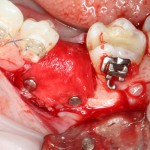

Несложная остеопластика в пределах 1-2 зубов занимает примерно столько же времени. При отработанном планировании и правильной подготовке, комбинированная остеопластика с от первого разреза до последнего шва вполне укладывается в 45-60 минут:

Не аппендэктомия за 7 минут, но все же…